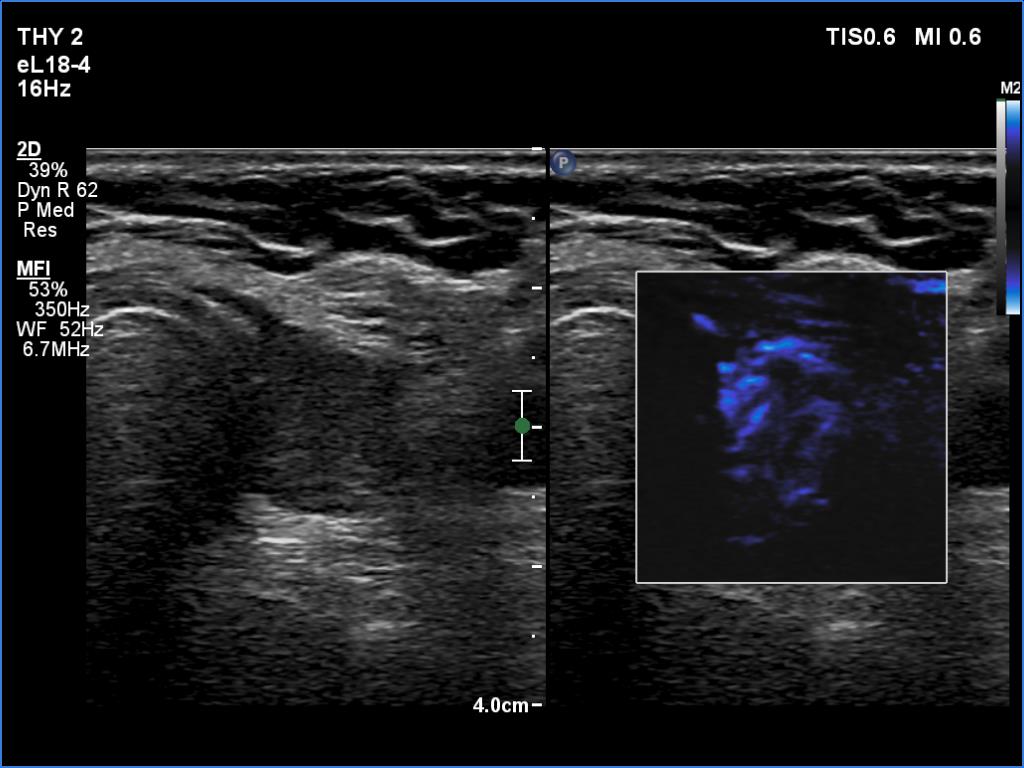

Follow-up investigation 6 years after first visit (ultrasonographic picture 8)

Left lobe, transverse scan, microflow imaging. This modality discloses the presence of vessels.